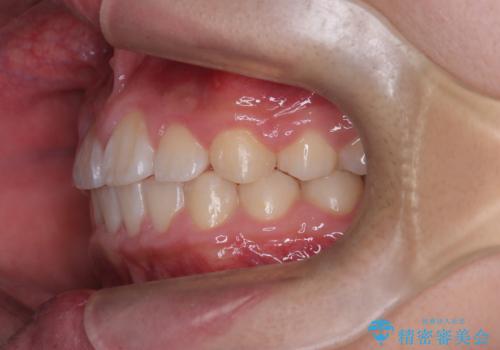

八重歯などの歯列のデコボコが綺麗に改善され、患者様にも大変喜んでいただけました。また、咬み合わせが深い「ディープバイト」も併せて改善し、見た目だけでなく機能面でもバランスの取れた咬合を獲得しています。

八重歯・歯並びのデコボコとディープバイトを改善した抜歯ワイヤー矯正症例

矯正の精密検査の結果上顎左右4番の計2本を抜歯し、審美性に配慮したワイヤー矯正装置(審美装置)を用いて治療を行いました。